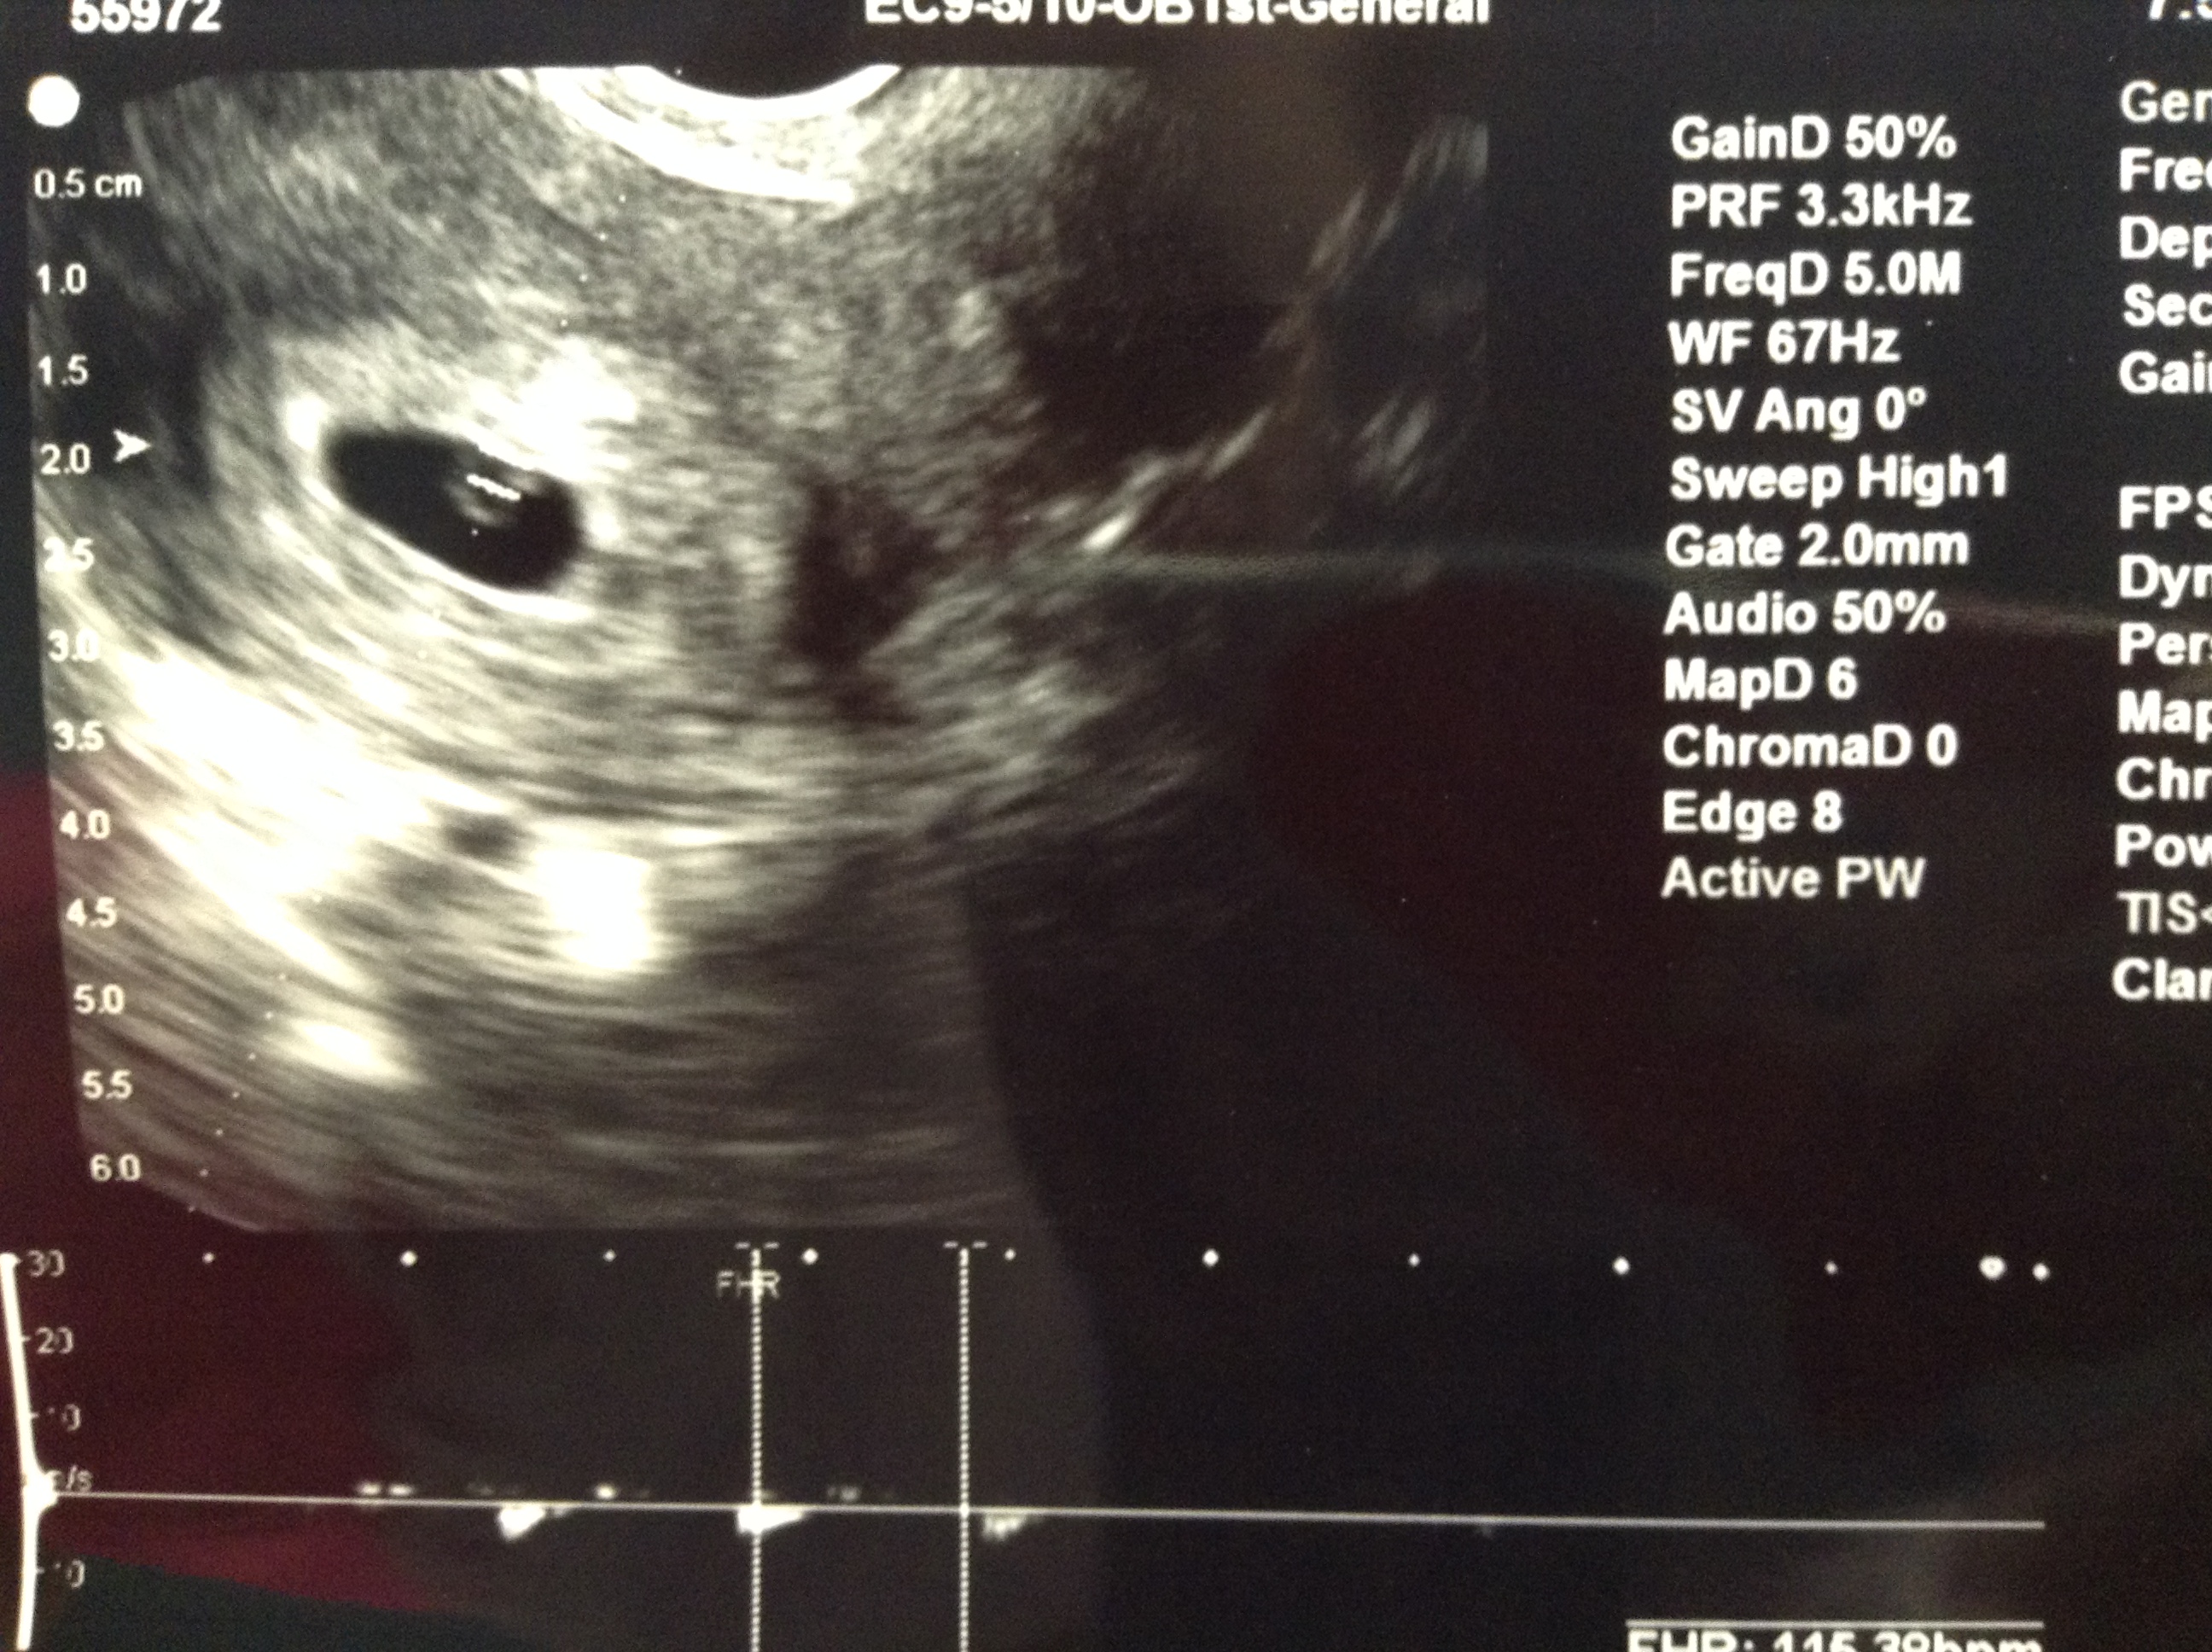

Okay so I am being a bit of an AW but...   I had an US this morning.  With my last pregnancy all I ever got to see was an empty sac so I kept fearing that that's what I would see.  Today DH & I go in & we got to see the yolk sac, fetal pole & a heart beat!  We even got to hear the heat beat which was really cool.  Heart beat is 115 bpm which she said is good & I am measuring right on schedule.  We've never made it this far which makes me excited & nervous at the same time.  Thanks for letting me be an AW!  :-)